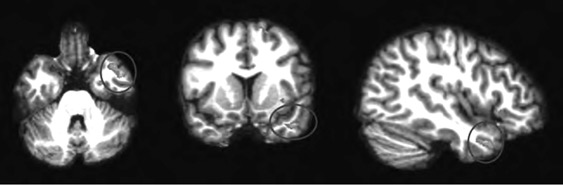

Анализируя далее научную литературу, мы пришли к выводу, что процесс поведенческого подражания с участием верхних отделов височной коры и эмоциональный (физиологический) резонанс, требующий участия островка, тоже имеют отношение к системе зеркальных нейронов. При подражании верхние отделы височной коры кодируют сложные процессы сенсорных следствий двигательных актов; при эмоциональном резонансе островок осуществляет физиологический и аффективный сдвиг, имитирующий его у другого человека. Исходя из параллелизма этих функций реципрокного действия (имитационной, физиологической и аффективной), мы можем использовать термин «резонансный контур», подразумевая, что в нем могут участвовать зеркальные нейроны, но не все компоненты этого контура двигательные, поэтому формально мы не можем назвать такой контур зеркальным. В нашем обсуждении мы примем во внимание это отличие и будем называть резонансный контур именно так, или будем прибегать к выражению «области, связанные с системой зеркальных нейронов» (рис. П.1 и П.2).

П.1

П.2

Рис. П.1, П.2. Функциональная МРТ, выполненная во время выполнения медитации осознавания дыхания. На снимках видна активация верхней височной извилины (рис. П.1) и активация островка и вентрального отдела передней поясной извилины (рис. П.2). Верхняя височная кора, островок и области срединной префронтальной коры (показанные здесь) вместе с системой зеркальных нейронов, как предполагается в тексте, содержат элементы «резонансного контура», которые активируются в ходе внимательного осознавания (снимки напечатаны с разрешения Сары Лазар © 2005)